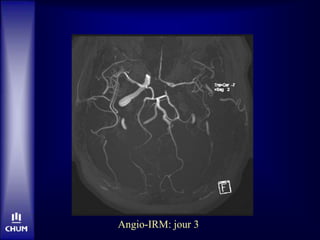

Jour 3

• Plus somnolent, mutique

• Parésie jambe gauche

Angio-IRM: jour 3

IRM: jour 3